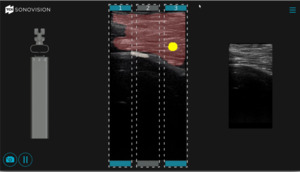

While EMG may provide some insight regarding the location of key anatomical structures, it still does not meet the need for a real-time intraoperative imaging device. This represents an unmet clinical need for a device that provides surgeons with accurate intraoperative guidance that will help reduce the incidence of postoperative LLIF complications. In this review we will focus on the use of the SonoVision™ imaging system and the Beluga1™ probe (Figure 3) as a potential technology to address the unmet clinical need for real-time intraoperative imaging.

2.2 Introduction to Device

SonoVision™ provides an answer to many of the unmet needs in terms of intraoperative imaging for spine surgery. The use of a machine learning algorithm and numerous rounds of data training allows SonoVision™ to differentiate between various soft-tissue types and structures (bone, nerve, and vascular structures). It uses this information to create a real-time overlay for high-quality ultrasound imaging which highlights and color codes key anatomical structures such as nerves, muscle, bone and blood vessels (Figure 4). While other devices may provide higher image resolution, the tradeoff of near instantaneous images, accurate identification of key soft tissue structures, and low risk and cost for the patient make this a more effective intraoperative imaging device.

The system utilizes a combination of a tubular stabilizer and ultrasound transducer. Once access to the appropriate disk space is established, the tubular stabilizer is inserted using the same incision site (2.5cm) and positioned over the disk space of interest. The ultrasound is then inserted through the tubular stabilizer and collectively locked into place (Figure 5). Correct positioning is confirmed via fluoroscopy (Figure 6). The real-time ultrasound image with SonoVision™ is then consulted to determine the most appropriate trajectory. The image provides a 25 x 40 mm viewing window and includes overlayed divisions that correspond to 3 potential trajectories available through the SonoVision™ dilator guide. Once a trajectory has been decided upon, the SonoVision™ transducer is replaced with the dilator guide (Figure 7), which features 3 numbered dilator paths corresponding with the 3 potential trajectories displayed on SonoVision™ (Figure 8). At this time, a guide wire can be inserted through the appropriate path in the dilator guide, followed by removal of the dilator guide and stabilizer tube and the use of sequential dilators.